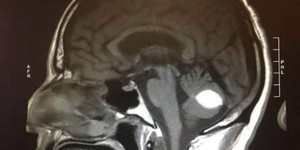

Với máy chụp cộng hưởng từ, chụp MRI, việc phát hiện sớm các khối u đã mang lại những tín hiệu mới trong việc điều trị bệnh của người dân.

Từ bỏ ca mổ rủi ro cao do khối u lớn ở giữa não, nhưng khi bé Nhi rơi vào hôn mê, gia đình quyết định thử vận may cuối cùng tại Bệnh viện K và phép màu đã đến.

Anh L.T.L. (38 tuổi, Bắc Giang) có khối u lớn ở trung tâm não, nhập viện trong tình trạng rất nguy kịch vừa được cứu.